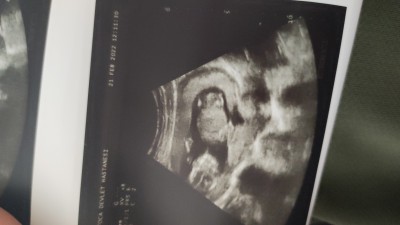

Hanımlar 15 haftalık. Sizce cinsiyet nedir tahmininiz var mı?

Gebelik haftası 15

Çizgiler + ise kız eksi - ise de erkek

Bende yeni öğrendim cinsiyeti bi tanıdık ultrason kağıdıma baktı hemen ddi eksi işareti var o zaman erkek ddi doğru da çıktı

Ultrason kağıdının köşesinde hemen var bende yeni öğrendim

Ultrason kağıdının hemen köşelerine bakın görürsünüz ben 3 buçuk aylıkken öğrendim